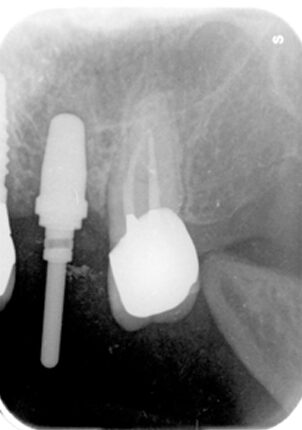

11.経過レントゲン

↑2006年4月24日

↑2008年12月

15.右下6番近心根抜歯(2016年12月12日)

↑術後1か月(2017年1月7日)

21.インプラント埋入後(2021年1月27日)

22.上顎左側6番補綴物装着(2021年10月23日)